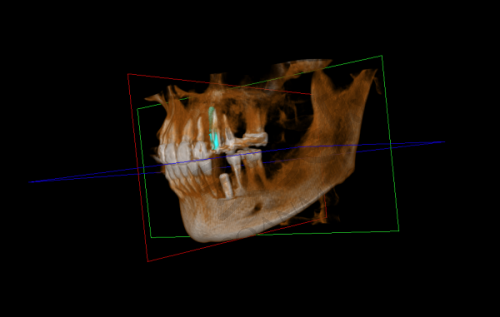

轮到我就诊时,医生非常和蔼可亲,他先仔细地询问了我的牙齿病史和目前的症状。然后让我躺在牙椅上,用专精的设备对我的口腔进行了全方面的检查。医生一边检查一边耐心地给我讲解我的牙齿情况,包括牙槽骨的密度、牙龈的健康状况等。通过详细的检查,医生发现我的牙槽骨条件还不错,这为种植牙手术提供了良好的基础。之后,医生为我安排了进一步的口腔 CT 检查,以便更正确地了解牙齿的内部结构。整个诊断过程非常细致,让我对自己的牙齿状况有了清晰的认识。

太原达美联合口腔医院的种植牙技术有特别多特色。首先,医院采用的是精良的数字化种植技术。通过口腔 CT 扫描和计算机模拟,医生可以严谨地规划种植体的位置和角度,大大提高了手术的成功几率。其次,医院的种植体品牌丰富,患者可以根据自己的需求和经济状况进行选择。再者,医院的医生团队会为每一位患者制定个性化的治疗方案,充分考虑患者的口腔状况和个人需求。末尾,医院提供完善的术后跟踪服务,医生会定期回访患者,了解修复情况并给予指导。